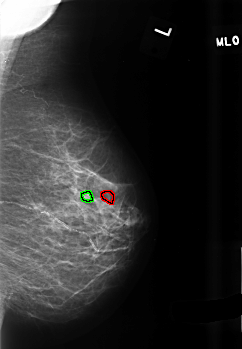

FILE: B_3435_1.LEFT_MLO.OVERLAY

TOTAL_ABNORMALITIES 2

ABNORMALITY 1

LESION_TYPE CALCIFICATION TYPE PLEOMORPHIC DISTRIBUTION CLUSTERED

ASSESSMENT 4

SUBTLETY 2

PATHOLOGY BENIGN

TOTAL_OUTLINES 1

BOUNDARY

ABNORMALITY 2